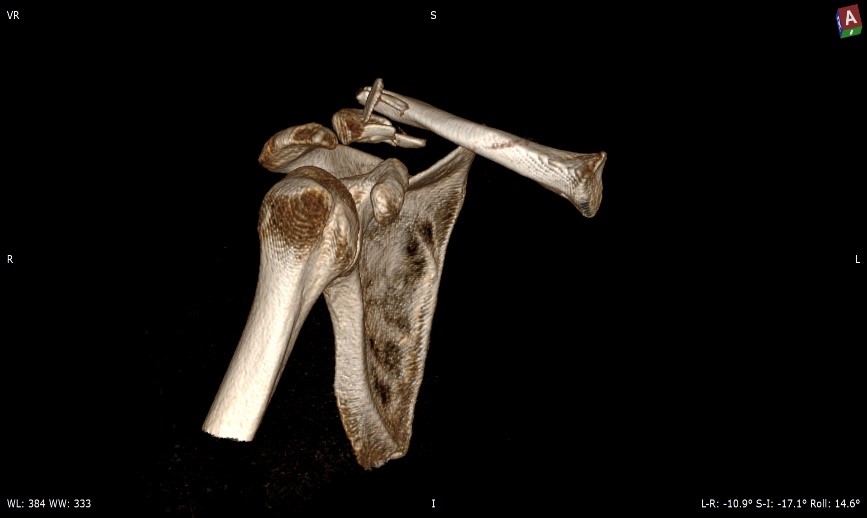

На скорости около 60 км/ч наш пациент после столкновения с легковым автомобилем, не имея полноценной защиты, получил оскольчатый перелом акромиального конца ключицы и незначительные повреждения – ушибы и ссадины.

Операция выполнена на следующий день. Выбрана самая стабильная фиксация: крючкообразная пластина для акромиального конца ключицы позволяет восстановить длину и форму самой ключицы, а также убрать нагрузку со связок акромиально-ключичного сочленения, способствовать их сращению заведением крюка под акромиальный отросток лопатки, то есть перенеся в эту точку напряжение с винтов пластины.